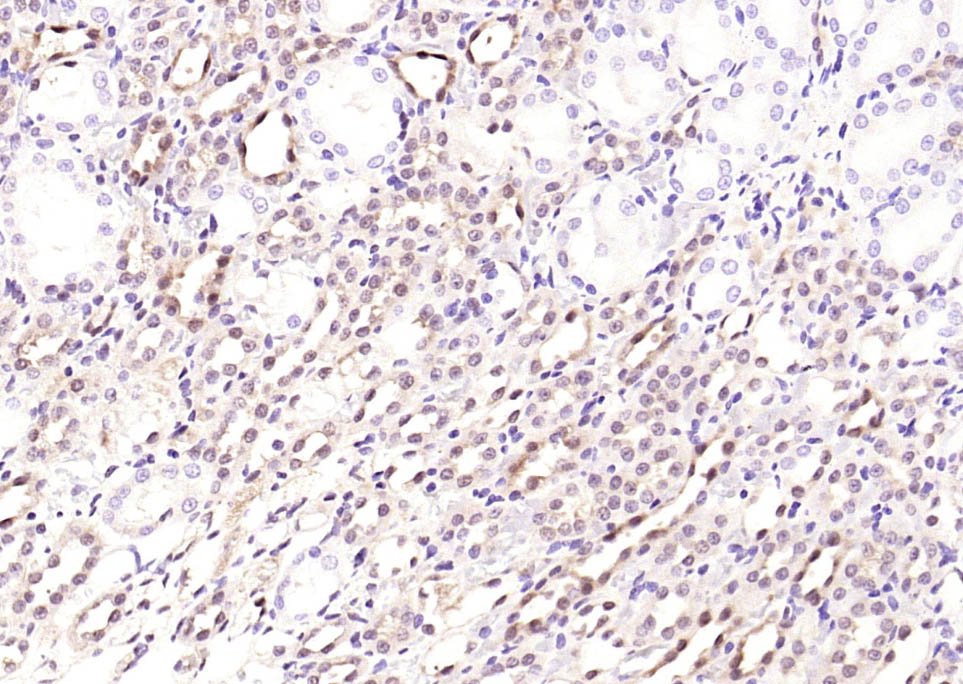

| IHC-P | Human, Mouse, Rat | Cow | 1:200-2000 |